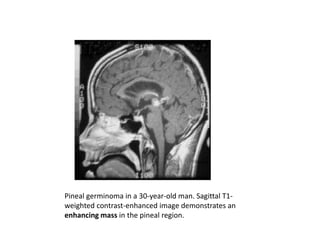

MASS IN THE PINEAL REGION.

Pineal germinoma in a 30-year-old man. Sagittal T1-

weighted contrast-enhanced image demonstrates an

enhancing mass in the pineal region.